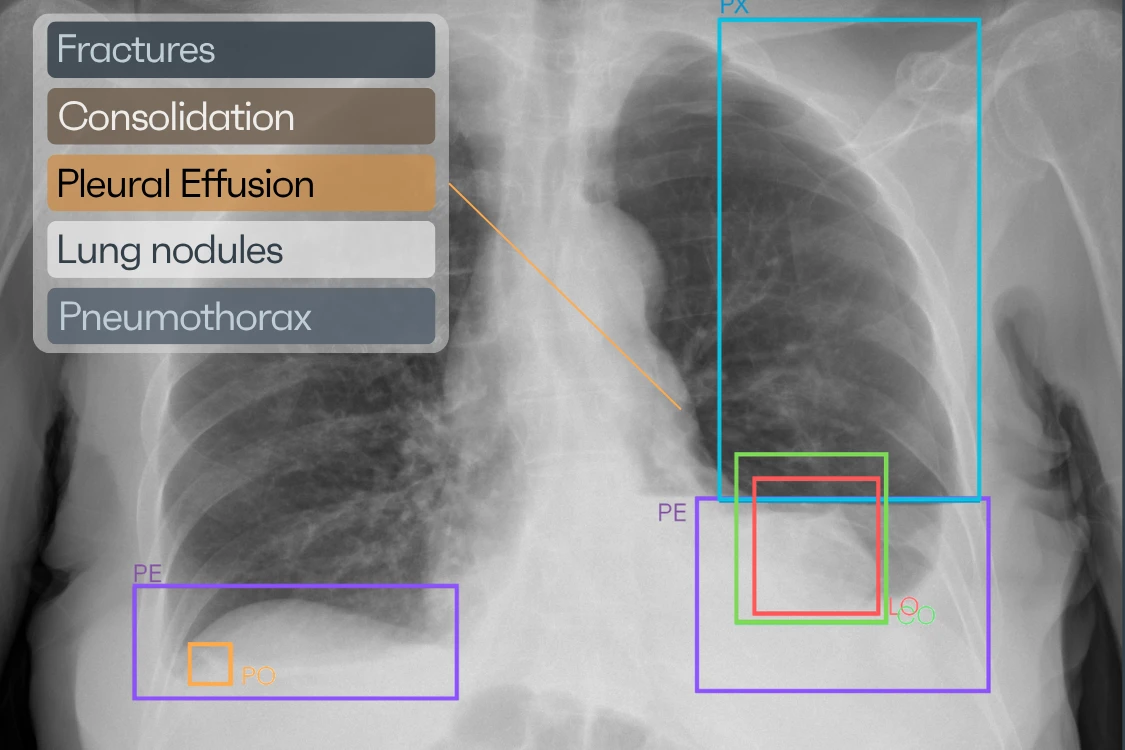

Radiology departments and outpatient imaging centers review a wide range of chest X-rays every day, from chronic disease monitoring and pre-operative assessment to general diagnostic workup. Rayscape CXR supports efficient, reliable review by helping identify clinically relevant thoracic abnormalities such as consolidation, interstitial patterns, nodules, pleural findings, and cardiac silhouette changes, while providing structured outputs.

CASE PRIORITIZATIONRAYSCAPE CXR AI brings computational clarity to everyday imaging, continuously analyzing chest X-rays to surface clinically meaningful patterns that might otherwise remain buried in visual complexity. By combining broad abnormality detection with advanced image enhancement, the system helps transform raw imaging data into structured, actionable insight.